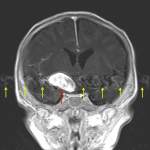

Age: 2 months

Sex: Female

Indication: Fussiness, bulging anterior fontanelle

MRI

Giant cerebral aneurysm